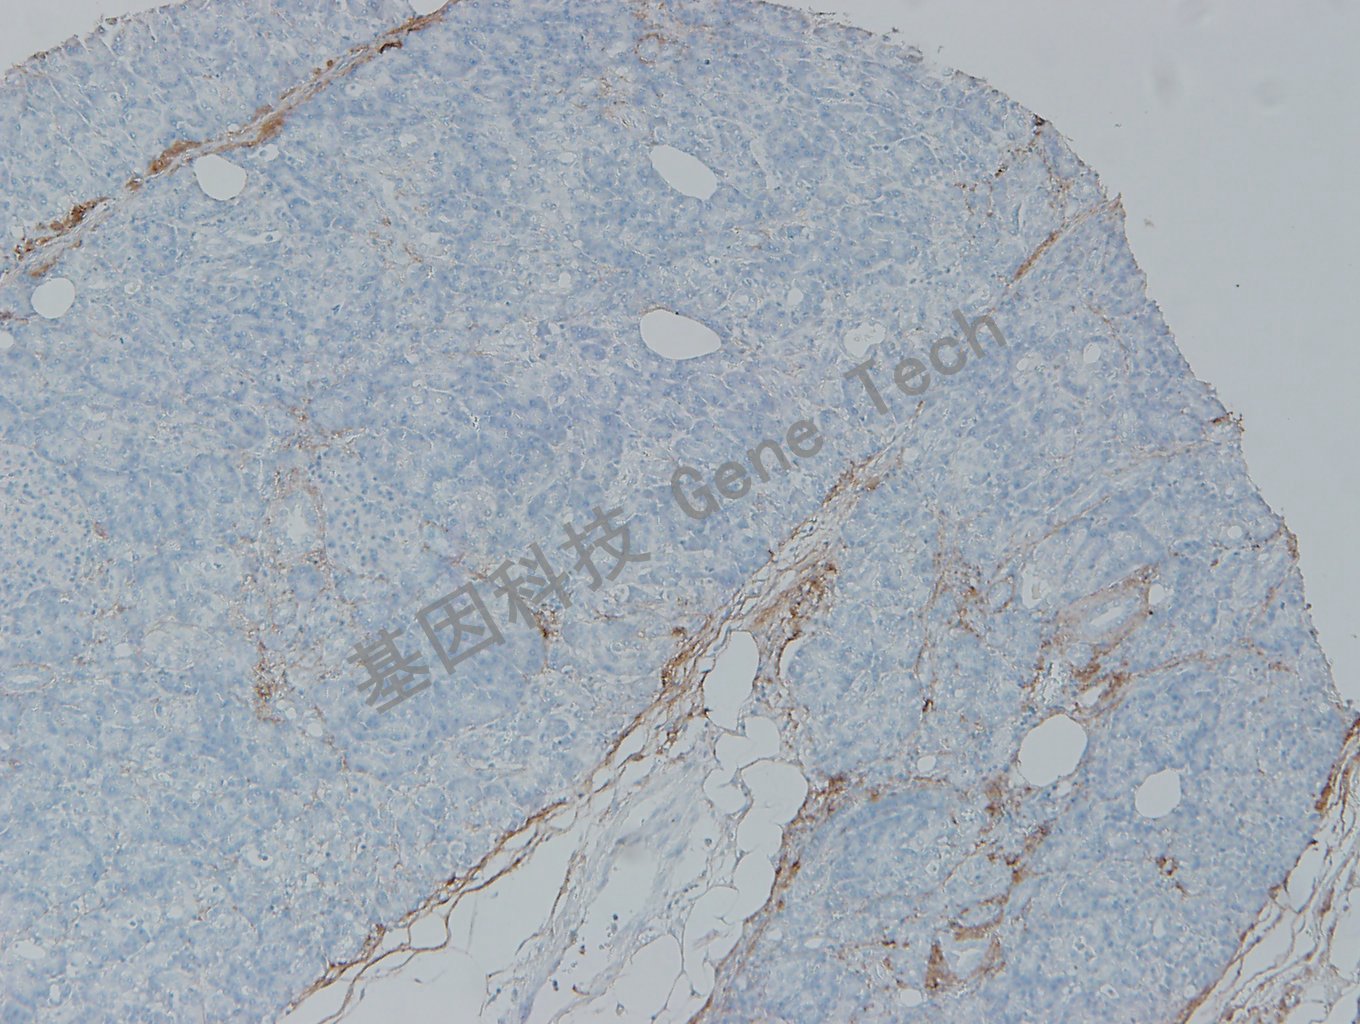

I 型膠原(CollagenType I)抗體 兔抗人 CollagenType I

| 克隆號:EP236 | 陽性對照:骨肉瘤/胰腺 | 陽性部位:細胞漿 |

| 預(yù)處理:高pH熱修復(fù) | 適用:石蠟切片/冰凍切片 | 顯色系統(tǒng):GTvisionTM |

| 簡介:I 型膠原主要由成纖維細胞、成骨細胞、成也本質(zhì)細胞和成軟骨細胞合成,主要存在于皮膚、骨骼、肌腱和其它結(jié)締組織中,是人體最豐富的細胞外基質(zhì)蛋白。 | ||

| 胰腺石蠟切片,用CollagenType I(GT2401)染色,細胞漿陽性,DAB 顯色。 | ||